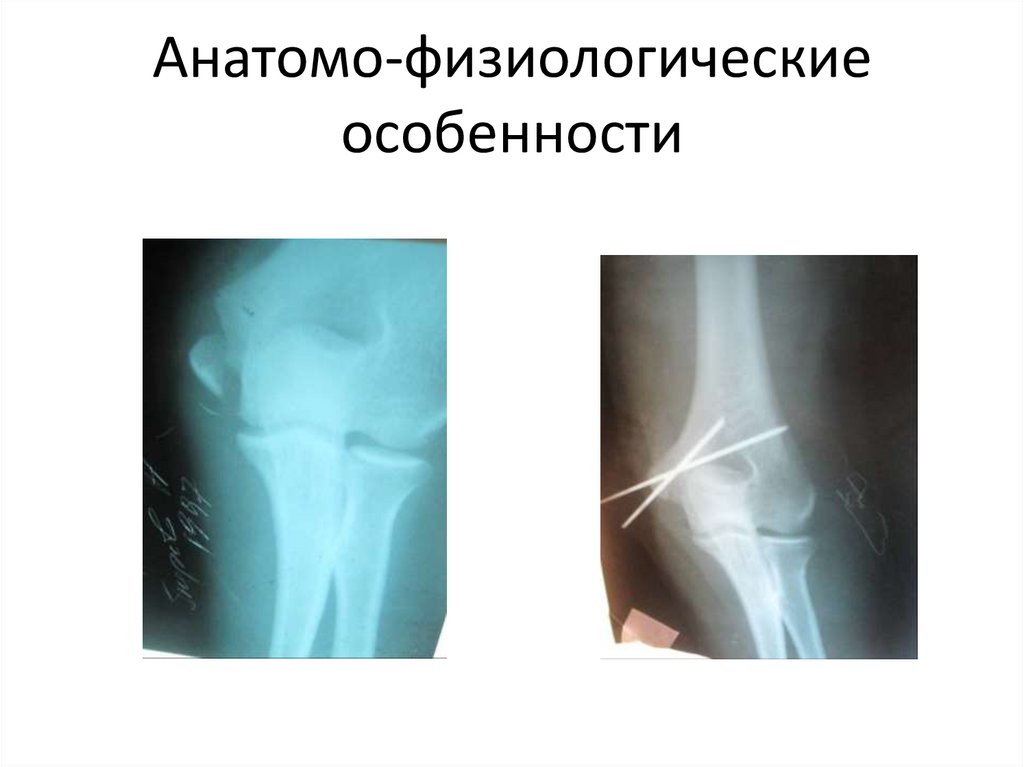

Анатомо-физиологические

особенности

65.

66.